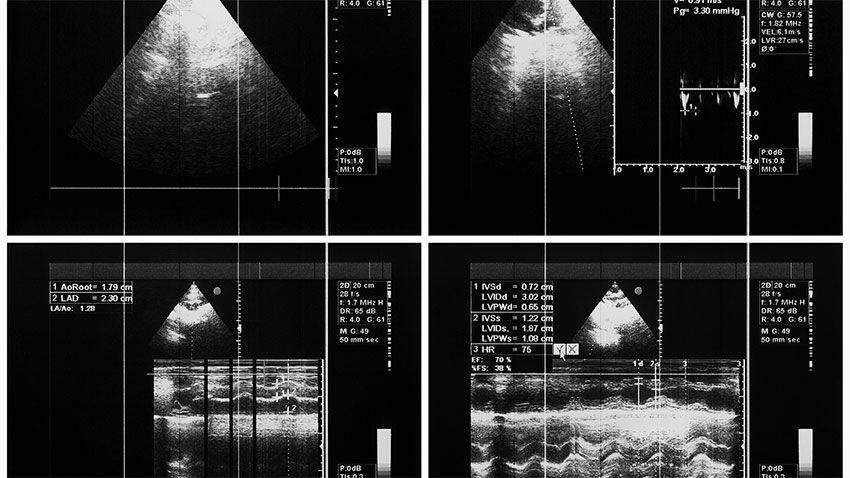

Explore Our Main Services

When you visit one of our state-of-the-art clinics we will make your examination as comfortable as possible with easy parking, spacious, private change rooms and comfortable waiting areas.